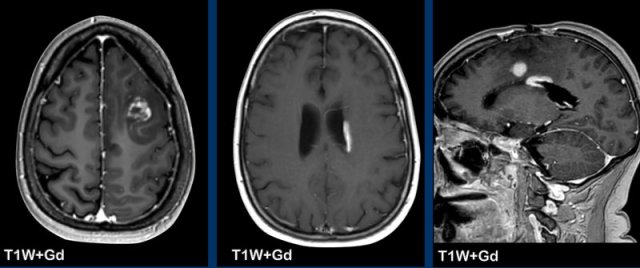

This is a patient with COVID infection, which was complicated by clotting problems and this resulted in multiple infarctions.

Notice the gyral pattern of the enhancement.

Continue with more images of this patient...

Again notice the gyral enhancement on the T1W+Gd images as a result of luxury perfusion and notice the widespread diffusion restriction on the DWI-images.

Can you tell which vascular areas are involved?

These areas are called the watershed or border zone areas.

A border zone area receives a dual blood supply from the most distal branches of two large arteries.

In times of systemic hypoperfusion, such as in disseminated intravascular coagulation or heart failure, these regions are particularly vulnerable to ischemia because they are supplied by the most distal branches of their arteries, and thus the least likely to receive sufficient blood.